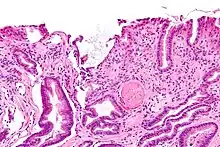

Micrograph showing gastric antral vascular ectasia. A large spherical, eosinophilic (i.e. pink) fibrin thrombus is seen off-center right. Stomach biopsy. H&E stain.

GAVE is usually diagnosed definitively by means of an endoscopic biopsy.[6][7][10][20] The tell-tale watermelon stripes show up during the endoscopy.[7]